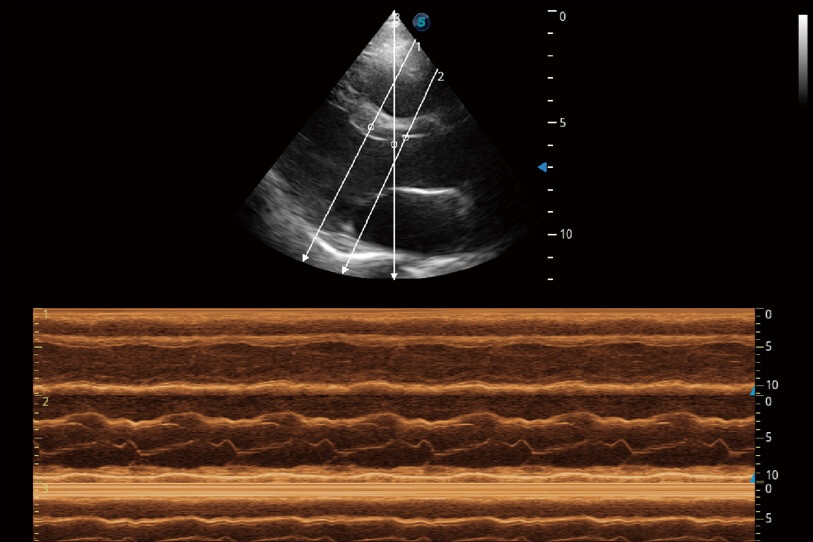

通過(guò)360度任意調(diào)節(jié)3條M型取樣線,在同一心動(dòng)周期上觀察心臟不同位置的運(yùn)動(dòng)曲線,得到準(zhǔn)確的心功能測(cè)量數(shù)據(jù),有效評(píng)估心肌運(yùn)動(dòng)及左心室功能。

當(dāng)心臟測(cè)量結(jié)果超出正常范圍時(shí),可實(shí)時(shí)預(yù)警提示動(dòng)物醫(yī)生,減少疾病漏診概率。